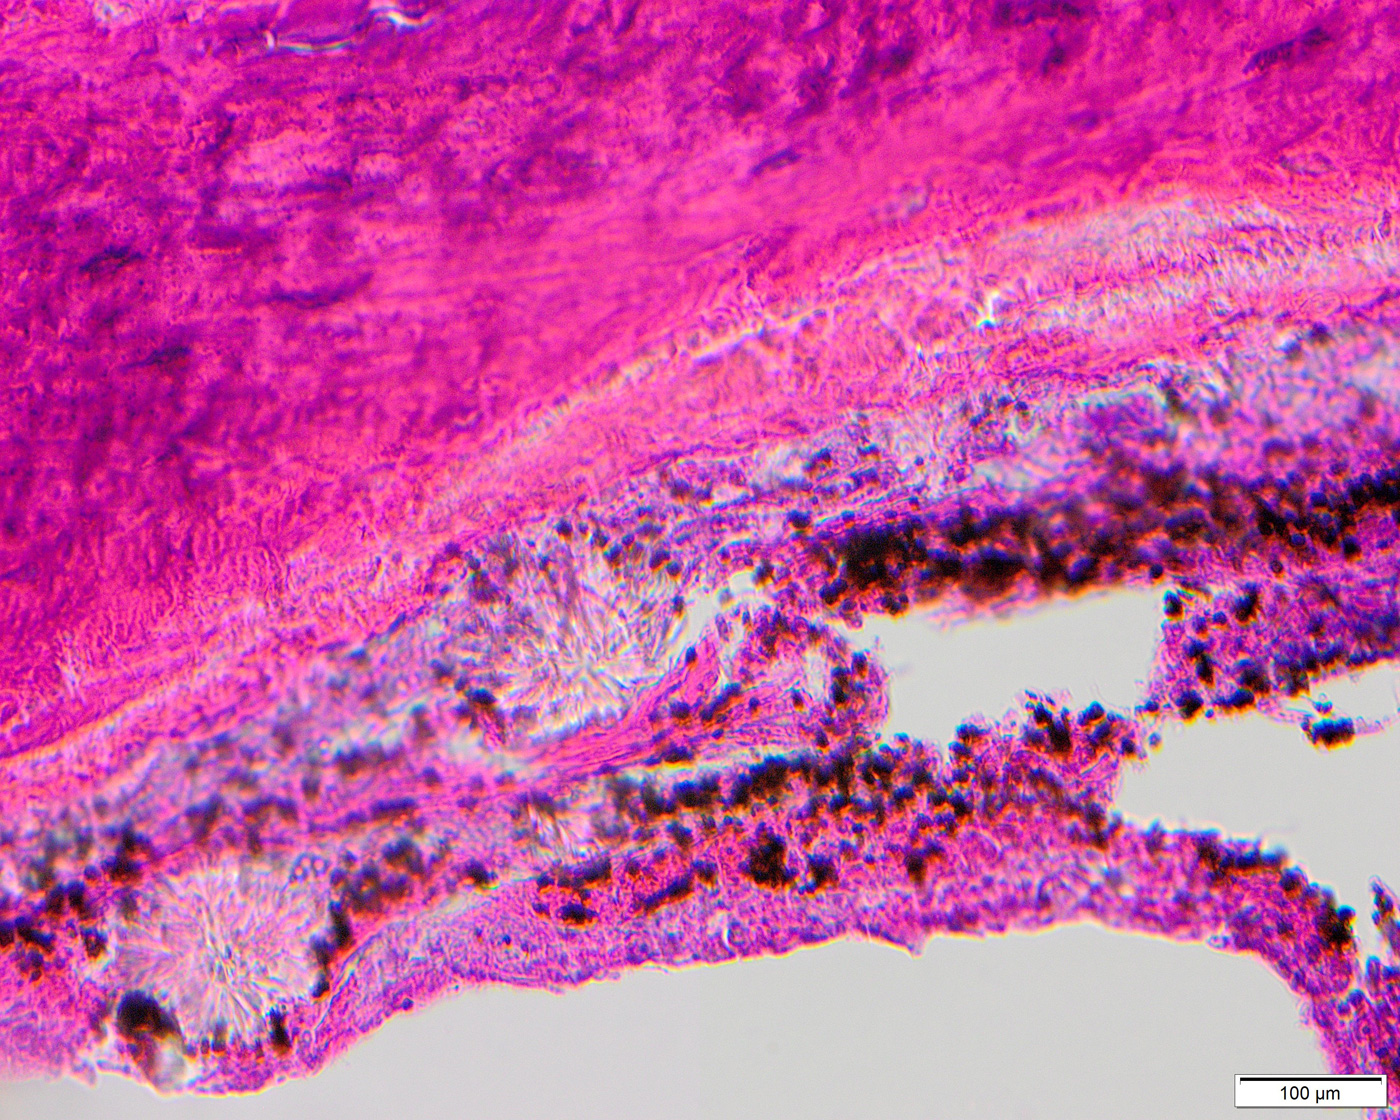

Histologic sections of the debrided tissue showed extensive necrosis of the sinonasal mucosa, soft tissue, and cartilage, abundant mixed inflammatory cells, and fungal organisms with features compatible with vascular invasion (Fig. 1). Intravascular thrombi (Fig. 1) and calcium oxalate crystals (Figs. 2 and 3) were also identified. The fungi were highlighted by GMS stain (Figs. 4 and 5) and displayed unpigmented septate acute-angle branching hyphae (Fig. 6) and fruiting bodies (fig. 7). Another fungal organism with wider hyphae, morphologically suggestive of Fusarium or Scedosporium was seen (Fig. 8). However, since no other fungi were isolated from culture, its exact identification remains unconfirmed.